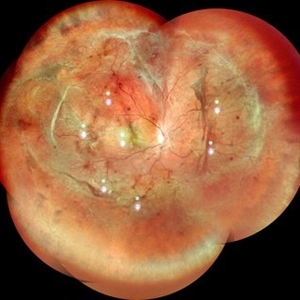

RPE rip in a case of Idiopathic polypoidal choroidopathy RPE rip in a case of Idiopathic polypoidal choroidopathyOct 23 2022 by Anjana Mirajkar, MS Ophthalmology Color photo wide field image in a of 61 year old male with RPE rip in a case of Idiopathic Polypoidal Choroidopathy. Photographer: Dr. Anjana Mirajkar -Retina Foundation, Ahmedabad Condition/keywords: RPE Rip